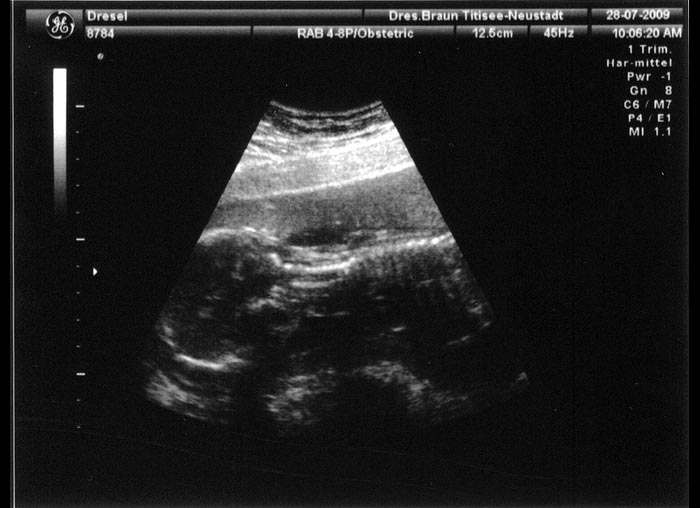

1. Ultraschallaufnahme